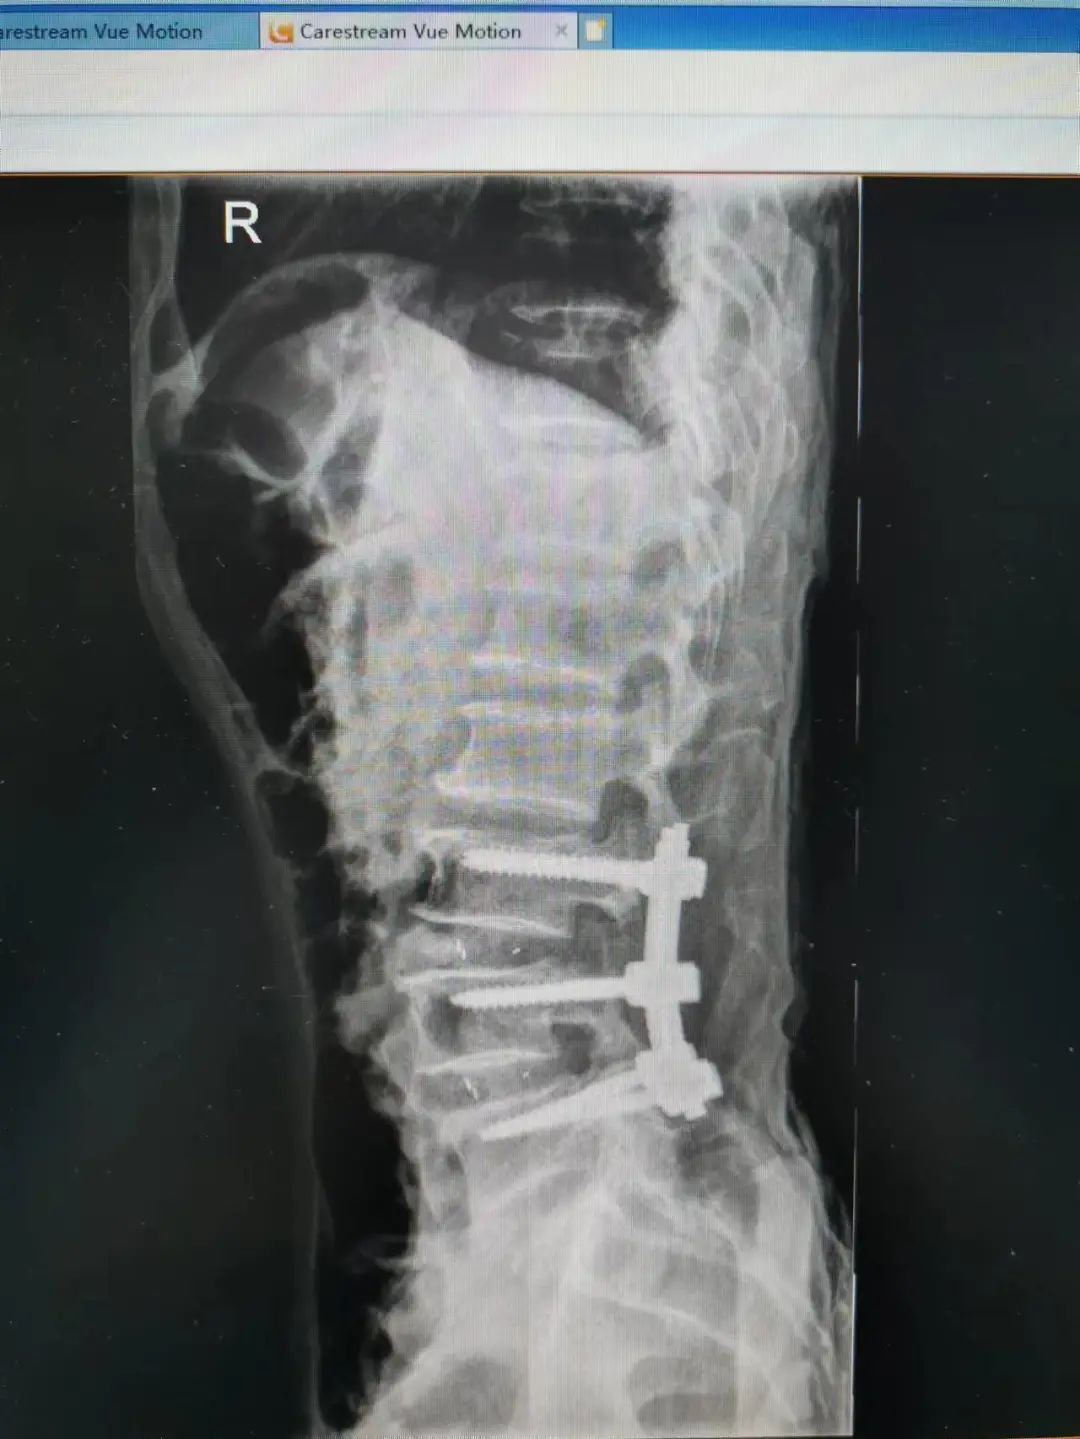

楊先生腰椎管狹窄癥拍片

由于楊先生的病情嚴重,需住院治療。楊先生入院后,瀘州市中醫(yī)醫(yī)院骨傷二科科主任楊陳一制定了手術(shù)計劃,決定脊髓型頸椎病的手術(shù)從前路切開減壓,頸3/4 、頸4/5、 頸5/6、 頸6/7椎間盤切除,椎間融合,鋼板內(nèi)固定術(shù)手術(shù),而腰椎管狹窄癥經(jīng)后路切開減壓,腰3/4、腰4/5椎同盤動除,椎間融合、釘棒系統(tǒng)內(nèi)固定術(shù)。